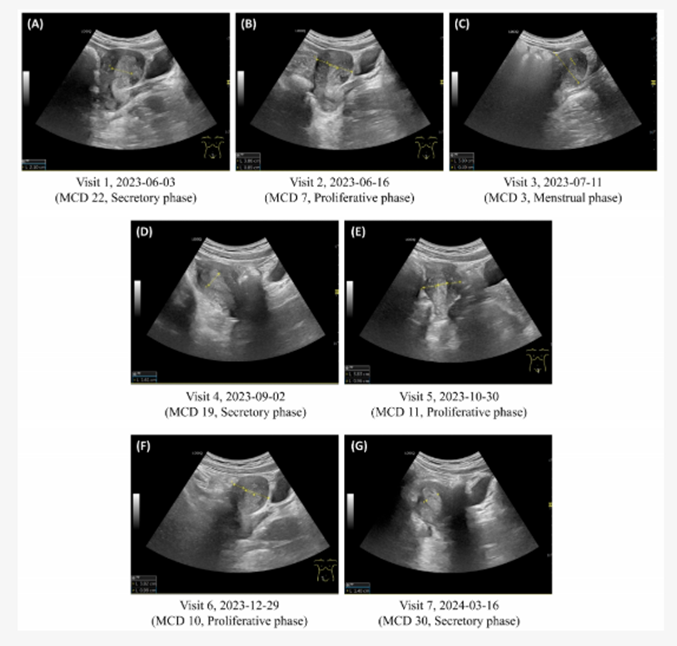

[한의신문] 대한한의사협회가 전국 3만 한의사들이 X-ray 사용에 본격적으로 나서겠다고 선언한 가운데 노스텔라 원장(기린한의원)이 자궁내막증식증 환자가 한약을 복용한 후 호전되고 치료되는 과정을 초음파 진단기기를 통해 7개월 이상 지속적으로 관찰한 논문을 SCI(E) 저널 Life(IF 3.2)에 게재했다. 본란에서는 노스텔라 원장에게 연구의 주요 내용과 의미를 들어봤다. <편집자 주>

A. 생리기간 단축 및 생리양 감소, 배란기 몸살, 위장장애 및 두통 등의 가장 큰 증상이었는데요. 배란기 몸살이나 통증은 NRS 7~8에서 0~1로 모두 호전되었습니다. 한약복용이 통증관리에도 효과적이지만, 특히 생리기간이 4일에서 6일로 다시 회복되고, 생리양 많은 날 사용하는 패드양이 중형 2~3개에서 대형 4~5개로 증가되어 생리양이 원상복귀되는 변화는 주목할 만합니다. 또한 작은 근종도 하나 있었는데, 한약투약으로 근종의 사이즈가 증가하지 않은 점이나, 수술, 소파술, 호르몬제 투약 없이 내막증식증이 한약으로 호전되고 유지된 점 또한 의의가 있습니다.

A. 미혼여성이라 자궁에 칼을 대고 싶어 하지 않았는데, 심지어 내막증 확진을 위한 생검도 원치 않으셨습니다. 한약투여로 전신증상뿐만이 아니라 생리기간, 생리양도 회복되고 이러한 변화를 초음파로 직접 눈으로 확인할 수 있어서 좋았던 듯합니다. 특히 어머님이 많이 좋아하셨어요.

A. 한의학에 대한 폄훼가 만연한 현 상황에 논문을 통해 꾸준히 증명하고 싶은 것이 있습니다. 각종 부인과 질환에 한의학적인 치료가 매우 효과적이며 실제 자궁변화와 연결된다는 것을 치료전후 초음파영상을 통해 보여주고 싶습니다.